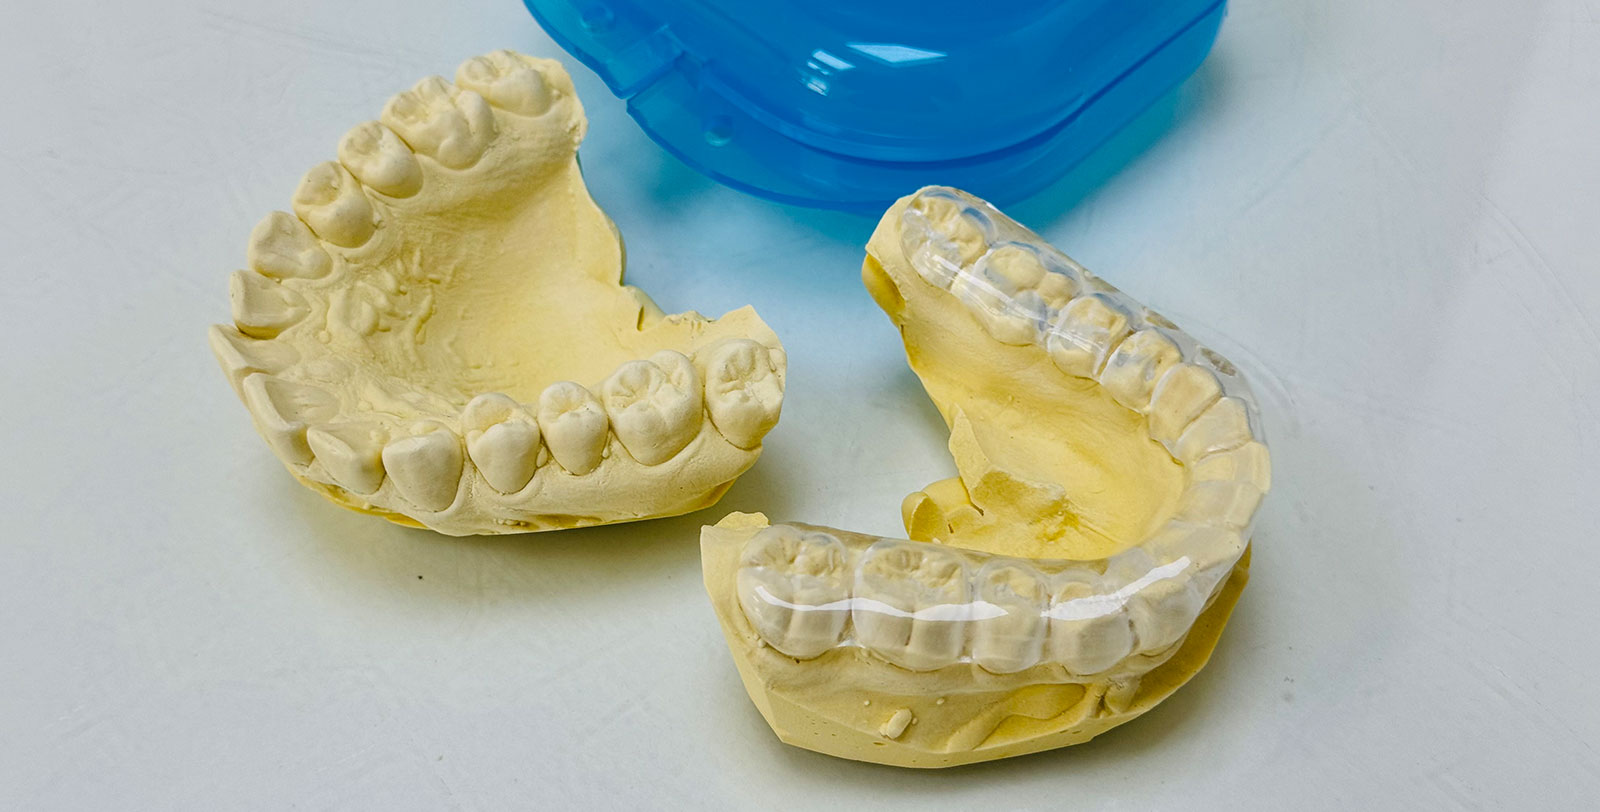

- Застосування міорелаксуючих кап сплінт-шини, які допомагають знизити навантаження нижньощелепного суглоба і запобігають скреготу зубів (бруксизм).